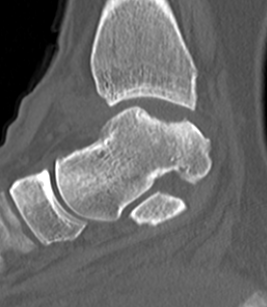

Posterior process fractures

Anatomy

Posterolateral & Posteromedial tubercles

- separated by sulcus for FHL

- lateral larger than medial

PL tubercle

- size variable

Fracture talus through articular cartilage into subchondral bone

- 2° force transmitted from distal tibia

Osteochondritis dissecans v osteochondral fracture

6% ankle sprains

Average age = 25

M > F